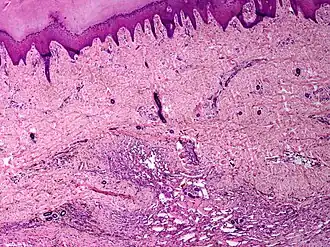

Description de cette image, également commentée ci-après

angiomatose cutanée

L'angiomatose est une maladie qui se caractérise par l'apparition d'un nombre important d'angiomes, c'est-à-dire de malformations des vaisseaux sanguins et des vaisseaux lymphatiques. Ces malformations sont multiples et sont présentes à la surface de la peau ou dans la profondeur des organes. Quelquefois, elles sont associées à d'autres malformations.